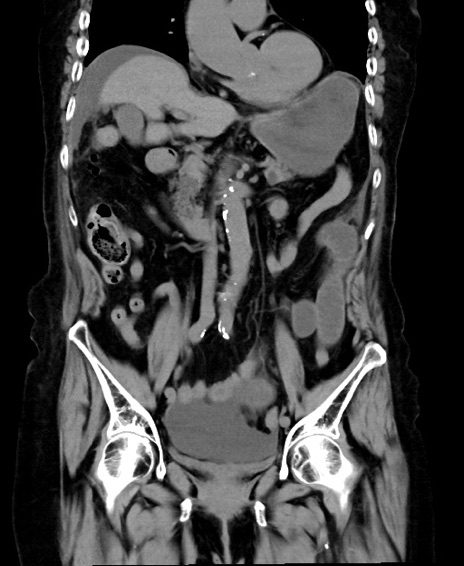

症例40(冠状断像)他院1日前

冠状断像